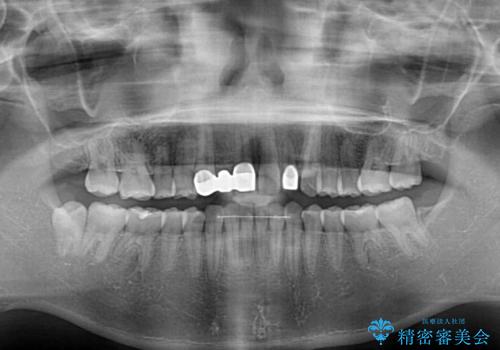

欠損による前歯のスペースが大きかったため、事前にワイヤー矯正で前歯の位置を大きく動かし、その後は上下をインビザラインで整えることとしました。

矯正治療後には欠損部はオールセラミックブリッジに、矮小歯はオールセラミッククラウンにて補綴することとしました。

前歯のスペースは、堅い線維の通った歯肉があり、幅も大きかったことから、歯肉切除を行った上でワイヤー矯正により移動を行いました。また、上唇小帯も歯間部付近まで付着していたため、合わせて切除しました。

ワイヤー矯正により、インビザラインよりも早く、歯軸の向きもコントロールしながら移動させることができました。